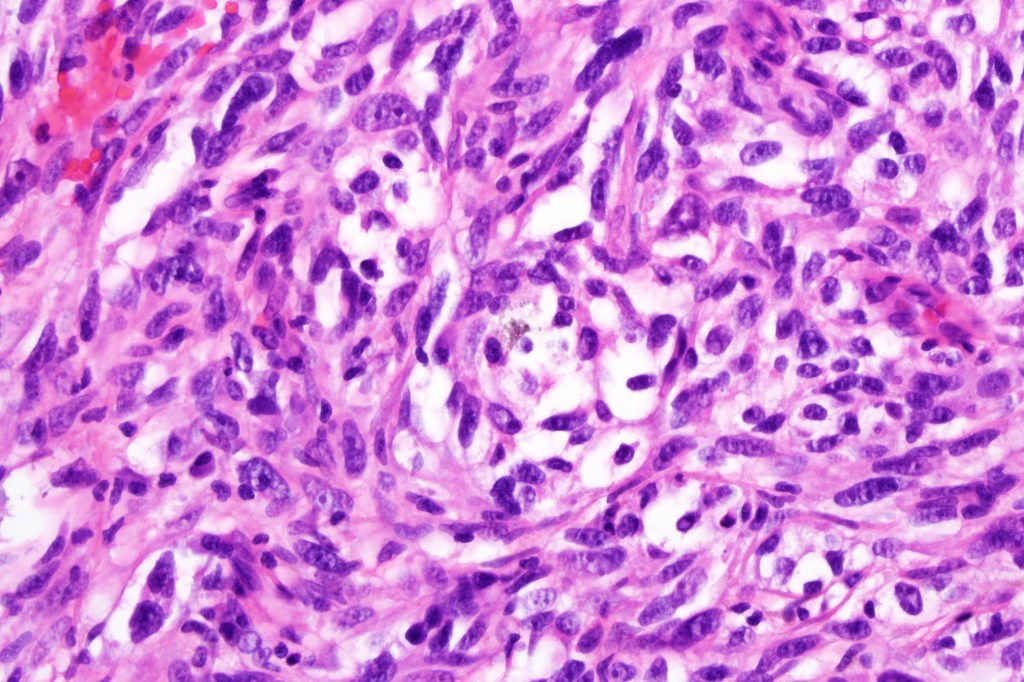

•Enlarged cells with copious eosinophilic, foamy or clear cytoplasm (some authors include melanoma with clear cell change in the same category)

•Nuclei vesicular or hyperchromatic

•Pleomorphism is not generally marked and indeed can be very subtle

•Variable mitotic activity